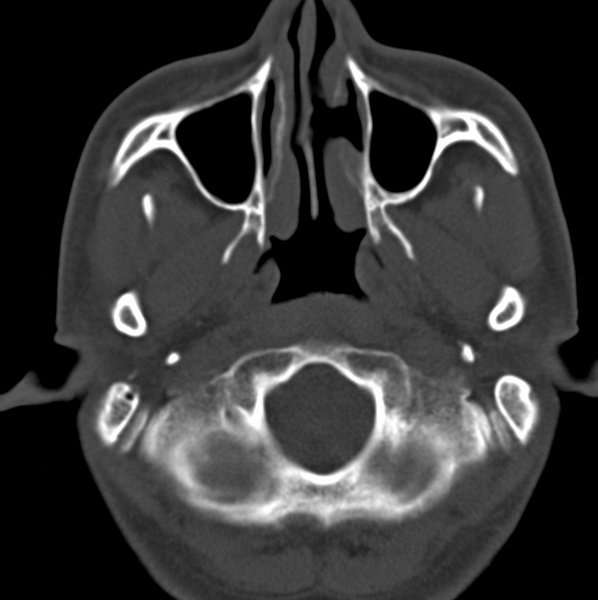

男、31、鼻咽部肿瘤放疗后请帮忙看看。

效果好,右侧破裂孔扩大,局部骨质缺损,为颅底骨质破坏。

1)鼻咽部肿瘤侵犯颅底放疗术后改变。2)左侧蝶窦炎。

咽后壁增厚,左侧咽鼓管隆突增大、咽鼓管咽口变浅,同侧咽旁间隙较窄。右侧颅底骨质破坏?为什么不在同一侧?

鼻咽部肿瘤侵犯颅底放疗术后改变.